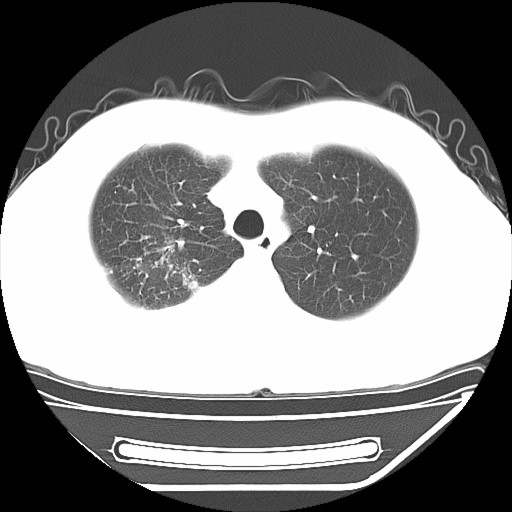

男,32岁,多年前右上肺结核,近期胸部不适,ct检查次序如上,上传主要层面,纵隔未见明显肿大淋巴结。

本人初次(2008年12月20日ct片)诊断为右上肺结核伴右侧胸水!保守治疗后,遂复查ct胸水逐渐减少!最后(2009年05月18日)诊断为右上肺结核,右侧胸水吸收后伴包裹形成!从逐次ct检查上看,胸水吸收好转,只是从2009年05月18日ct片看到一个胸膜结节。临床医生及某肿瘤医院认为2009年05月18日ct片,右后胸壁结节,考虑为胸膜肿瘤!

本人还是倾向于右后胸壁的局限性包裹,胸膜结节密度不均匀,其内可见低密度区,考虑是由胸水吸收后胸膜增厚、粘连及周围肺组织包裹形成的征象;不倾向于胸膜肿瘤的诊断。